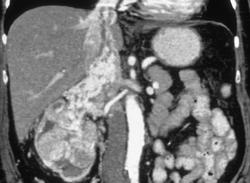

Renal Cell Carcinoma